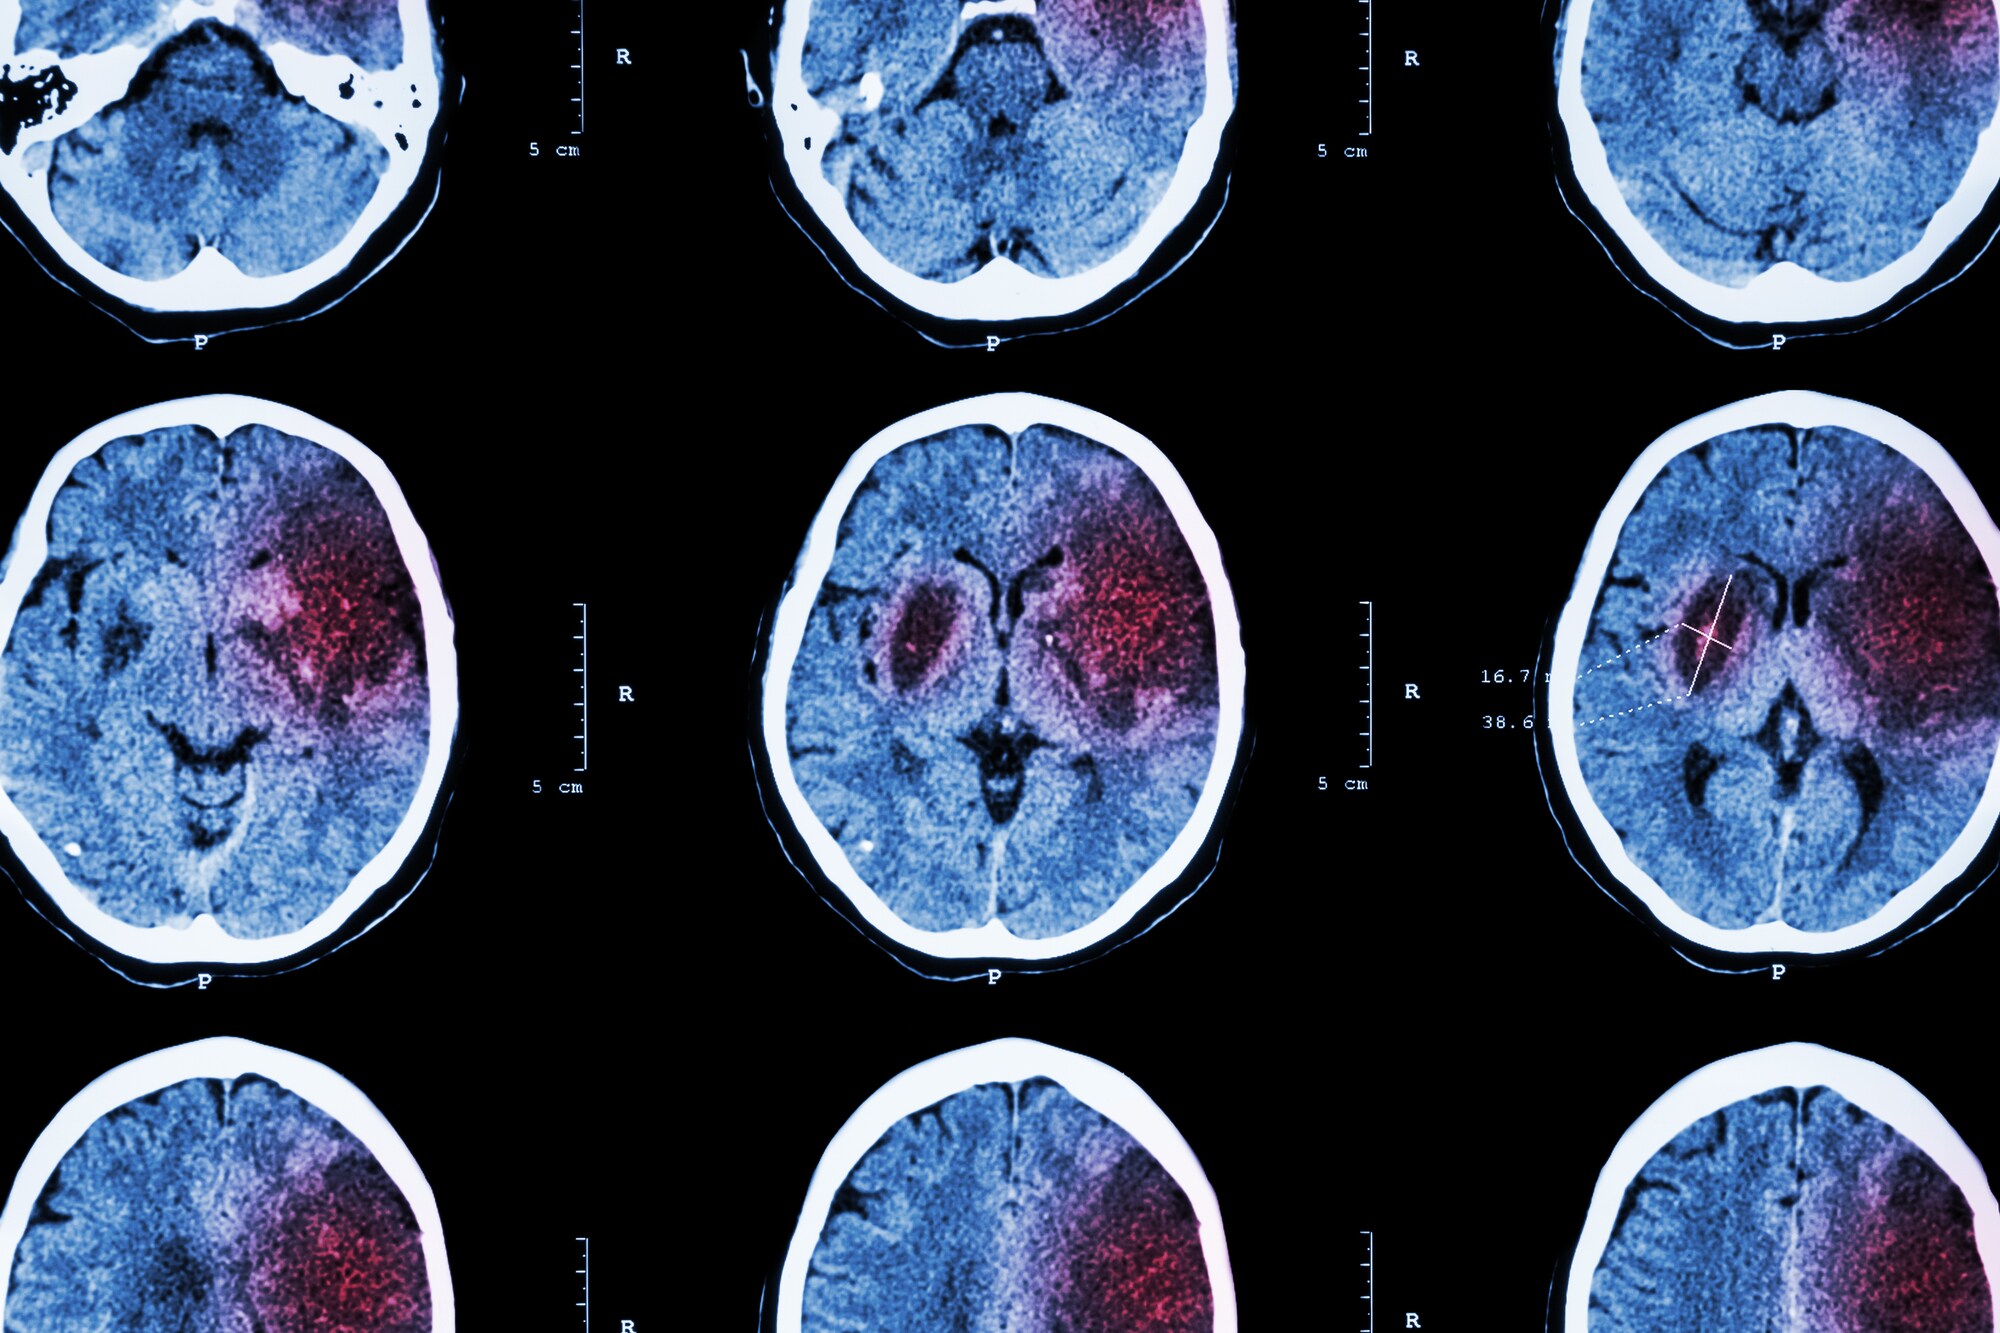

Αγγειακό εγκεφαλικό επεισόδιο